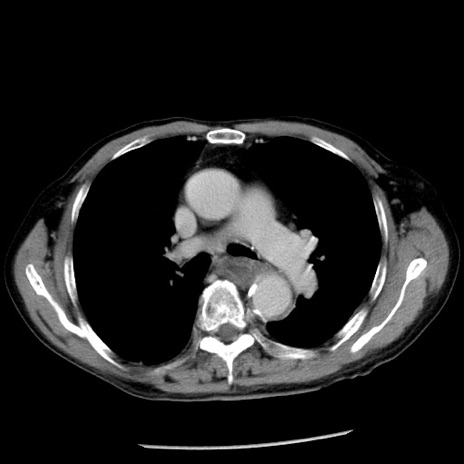

症例26(横断像)

【症例】80歳代男性

【主訴】嘔吐

【現病歴】昨晩2回嘔吐あり、今朝になっても嘔吐あり。来院。

【既往歴】胃潰瘍

【身体所見】意識清明、BT 37.6℃、BP 166/95mmHg、HR 100bpm、SpO2 97%、腹部:平坦・軟、腸蠕動音聴取良好、圧痛なし。

【データ】WBC 21900、CRP 1.46